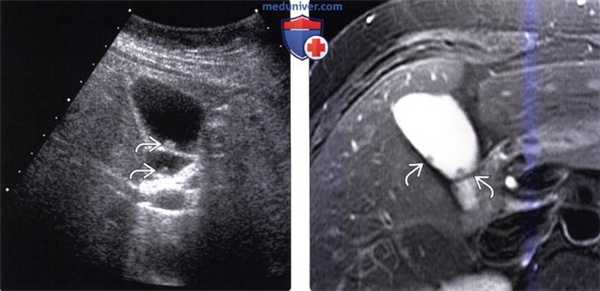

(Слева) На сонограмме у мужчины 43 лет визуализируются два мелких полипа в желчном пузыре. Оценка подвижности при исследовании в реальном времени помогает отличить полипы от небольших камней, не дающих акустической тени, и сладжа.

(Справа) На аксиальной Т2 ВИ FS МР томограмме у этого же пациента визуализируются два полипа, которые были обнаружены случайно два года назад и оставались стабильными в течение этого времени. Несмотря на то, что мелкие полипы редко являются злокачественными, при их обнаружении обычно назначается УЗИ в динамике. Продолжительность наблюдения и интервал между сонографическими исследованиями четко не определены.